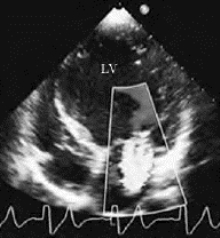

②多组瓣膜反流,以房室瓣口五彩反流束多见(图20-2)。

图20-2 扩张型心肌病彩色多普勒血流图(见彩图30)

图示左室明显扩大,二尖瓣中量反流